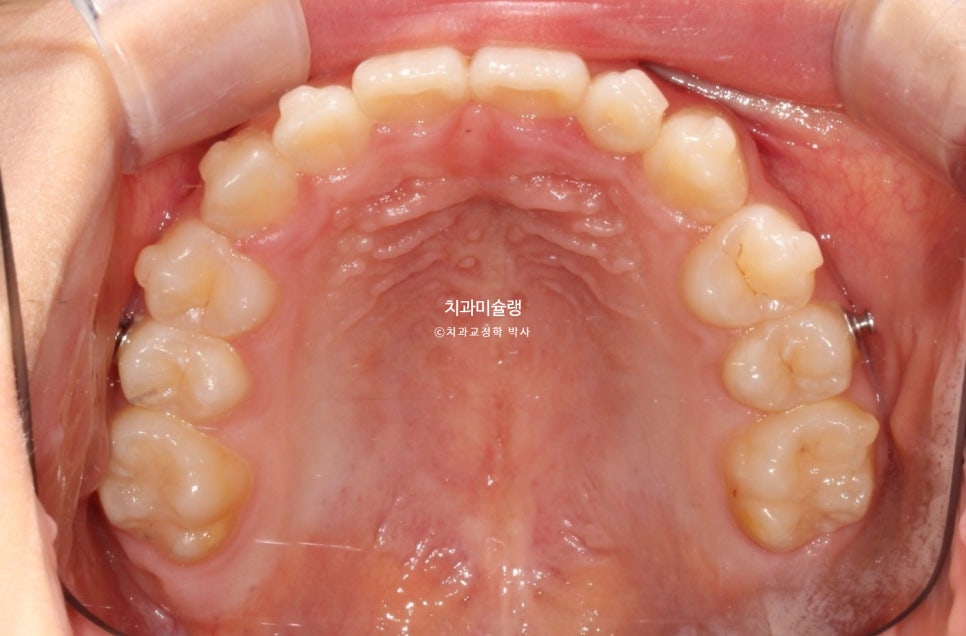

2026년 2월 – 치료 완료

2026년 2월, 정상교합이 달성되어 치료를 마무리 합니다.

중심선은 잘 맞으며 절단교합으로 인항 개방교합은 해소되었습니다.

어금니 교합관계는 1급을 달성.

3급 교합관계를 1급으로 만들기 위해 치료기간 내내 3급 고무줄을 사용했습니다.

결과가 성인교정치료 결과에 준한만큼 유지장치도 성인과 동일하게 들어갑니다.